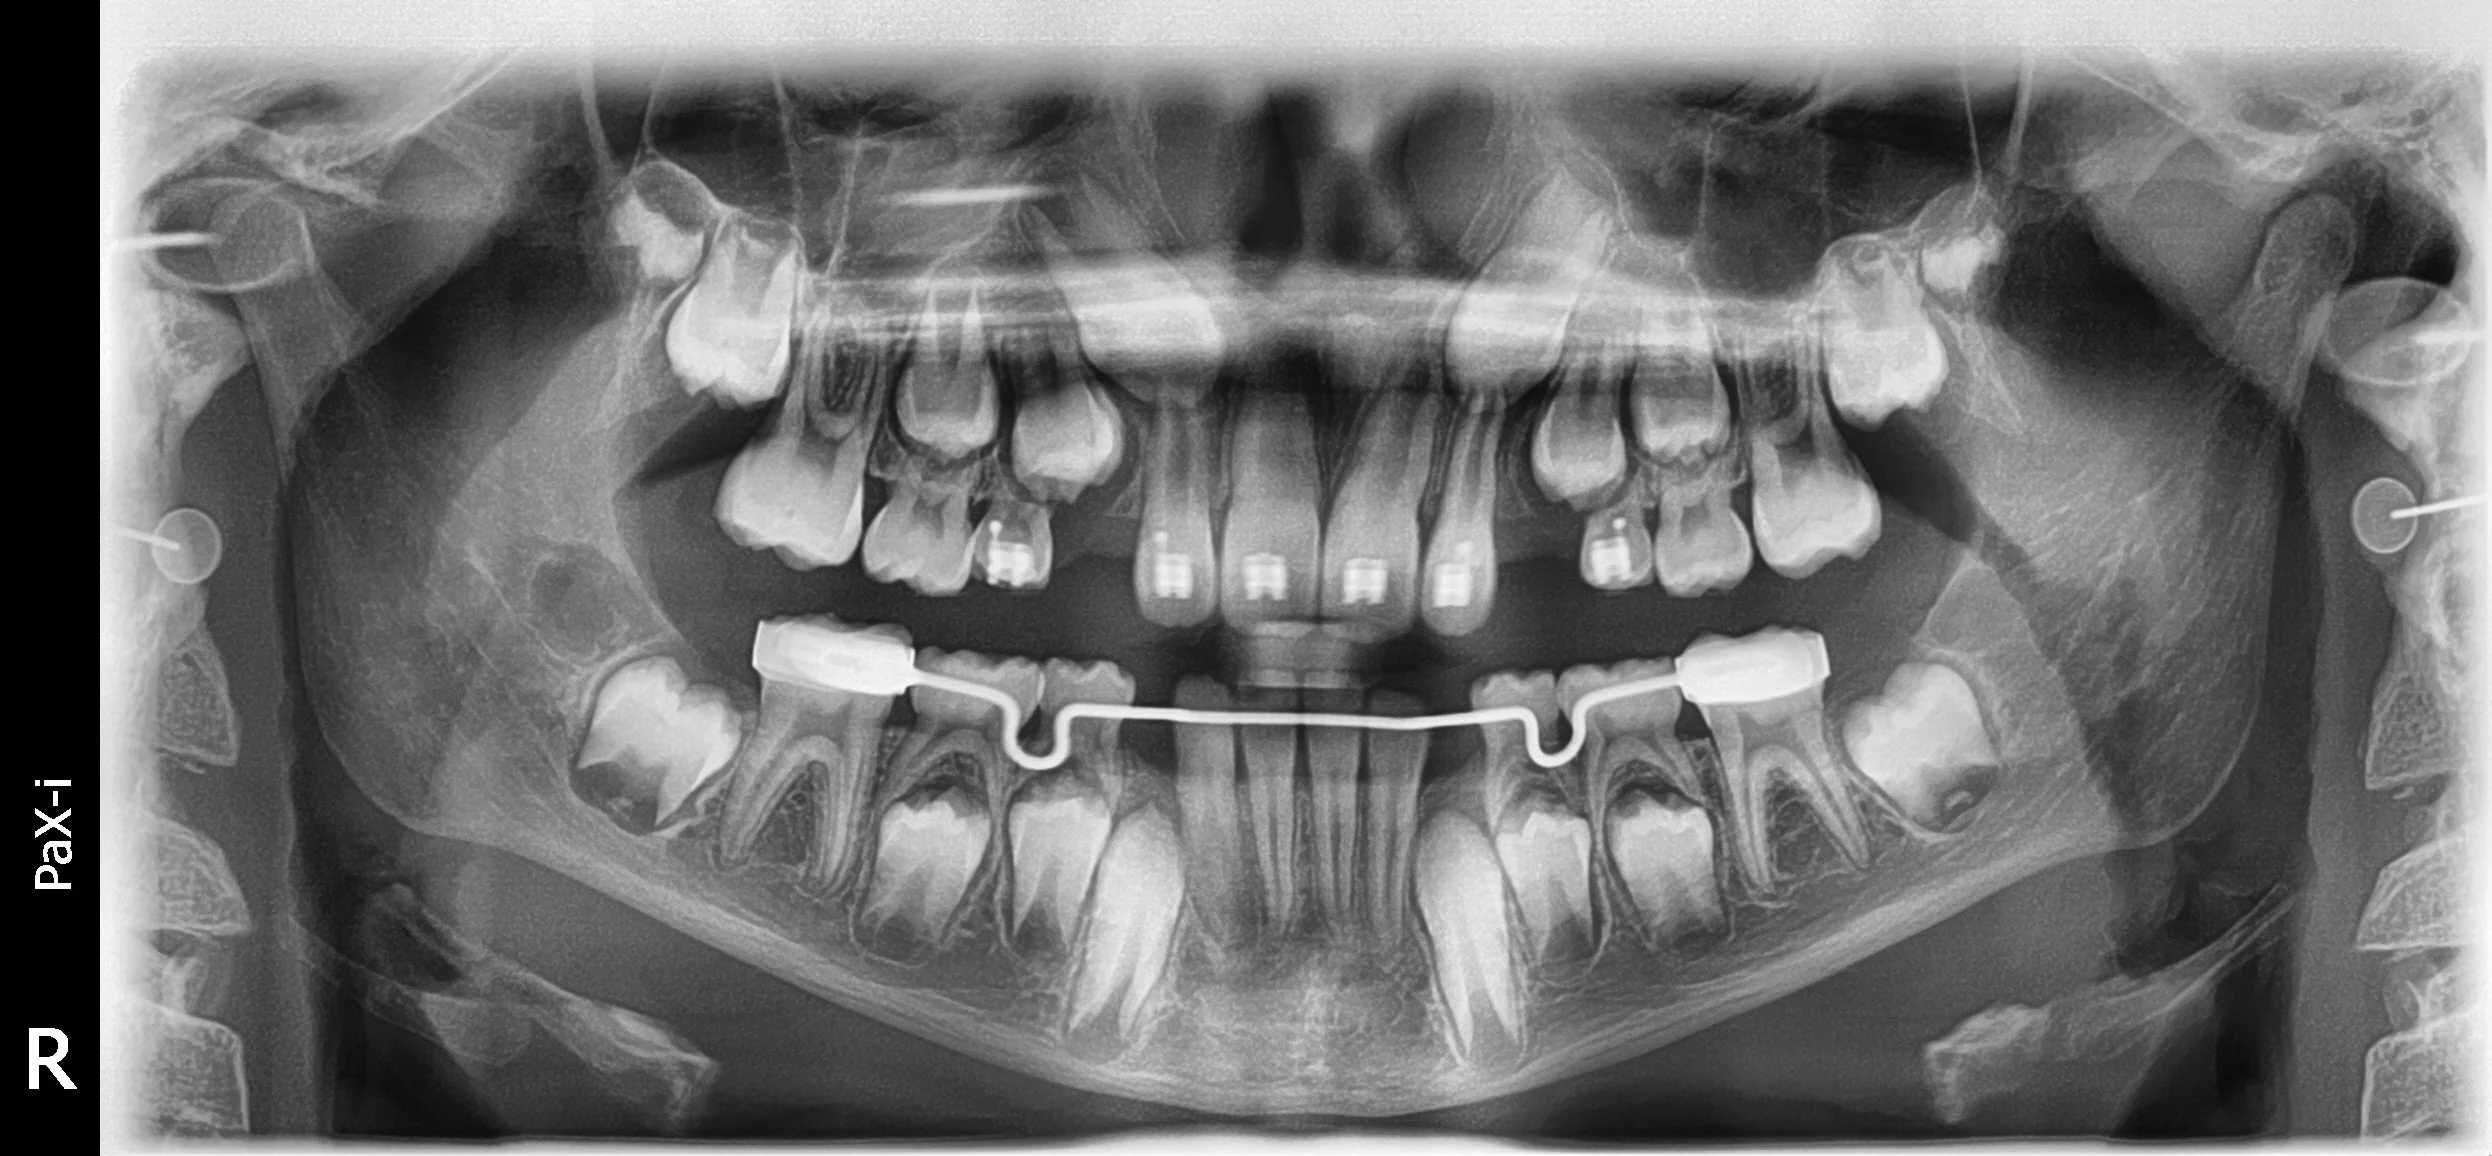

Panoramic X-ray image of a person's teeth showing orthodontic braces and impacted canines.

Start